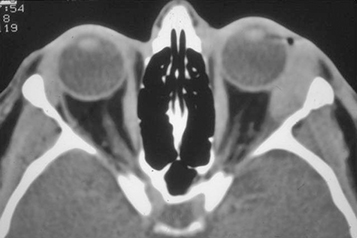

(See Figures 7.3.1.1 and 7.3.1.2.)

Eyelid edema, erythema, warmth, and tenderness. Conjunctival chemosis and injection, proptosis, and restricted extraocular motility with pain on attempted eye movement are usually present. Signs of optic neuropathy (e.g., afferent pupillary defect and dyschromatopsia) may be present in severe cases.

Decreased vision, retinal venous congestion, optic disc edema, purulent discharge, decreased periorbital sensation, and fever. CT scan usually shows adjacent sinusitis (typically at least an ethmoid sinusitis) and possibly a subperiosteal orbital collection.

Imaging: CT scan of the orbits and paranasal sinuses (axial, coronal, and parasagittal views, with contrast if possible) to confirm the diagnosis and to rule out a retained foreign body, orbital or SPA, paranasal sinus disease, cavernous sinus thrombosis, or intracranial extension. If superior ophthalmic vein or cavernous sinus thrombosis are suspected clinically, MRI with contrast and fat suppression should be obtained.